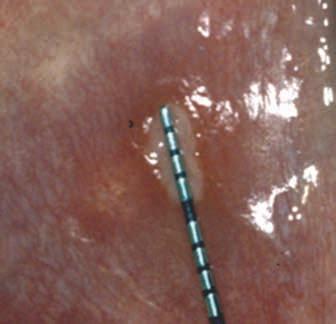

Vesiculobullous lesions occasionally occur on other mucosal surfaces such as the conjunctiva, genitals, skin, nares, esophagus, urethra, and rectum. Symblepharon formation (scarring extending from the conjunctiva to the eyeball itself) can lead to blindness (Figure 6). It is wise to refer patients for an evaluation by an ophthalmologist following diagnosis. Biopsy for routine histology and direct immunofluorescence is often necessary for a definitive diagnosis. Specimens will show a clean, sub-basilar separation of the epithelium from the underlying connective tissue.

Figure 6. Symblepharon (scar) in a patient with MMP extending from the conjunctiva to the eyeball. Figures 7 and 8. Erosions with ragged borders seen with pemphigus vulgaris. Figure 7 Figure 8